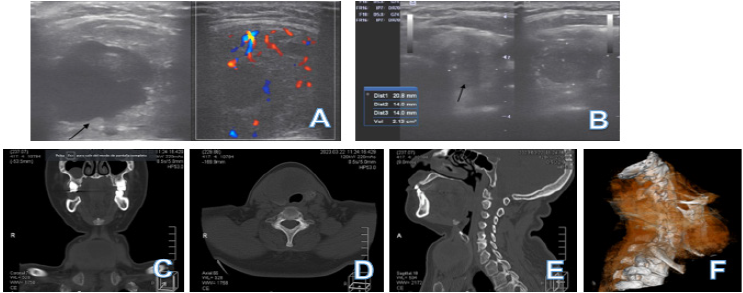

La ecografia tiroidea reportó tiroides aumentada de tamaño, asimétrica, de parénquima heterogéneo y ecogenicidad conservada.

Lóbulo derecho ocupado en su totalidad por nodulo redondeado ecomixto bordes regulares y definidos con degeneración quística a nivel central con Doppler central y periferico de 42.6x32.3x40.4 mm. (Figura 1A)

Lóbulo izquierdo con nodulo redondeado de bordes regulares y definidos, hipoecogénico, con calcificaciones puntiformes en su interior, con Doppler periferico de 20.8x14x14 mm; en tercio inferior nodulo hiperecogénico que deja sombra acústica posterior no vascularizado que mide 10.3x9.6 mm. (Figura 1B).

Volumen tiroideo total 22.14 cc.

Conclusión TI-RADS 4C.

La tomografía computarizada de columna cervical (realizada 4 meses posterior a la ecografía) evidenció alteración de la morfología tiroidea, con LOE que abarcaba lóbulo derecho e istmo, de 6.2x5.5x4.6 cm, redondeado, de bordes definidos, con áreas de densidad liquida focales de diametros variables, siendo la de mayor volumen central y tabicada, de 3.4x2.5 mm; tercio inferior del lóbulo izquierdo con nodulo hipodenso, redondeado, con calcificación periférica de 0.6 cm y nodulo en tercio medio y superior de 2.1x1.5 cm, lobulado, con calcificaciones lineales, centrales y periféricas. (Figura 1C-F)

Figura 1 A. Ecografía tiroidea del lóbulo tiroideo derecho. B. Ecografía tiroidea del lóbulo tiroideo izquierdo. C - F. Tomografía computarizada de cuello. E. Reconstrucción Tridimensional